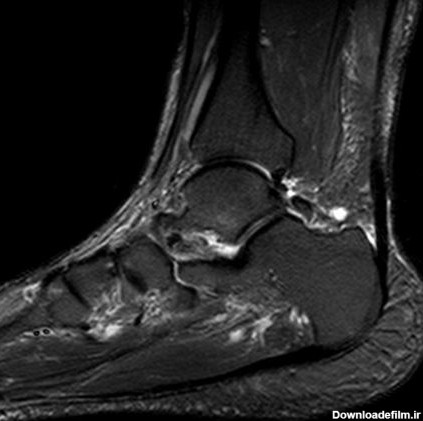

طرح ریزی انجام یک MRI مفصل مچ پا اندیکاسیون های انجام MRI مفصل مچ پا: ابنورمالی مغز استخوان: نکروز استخوان،

پیچ خوردگی مچ پا پیچ خوردگی مچ پا (رگ به رگ شدن) زمانی رخ میدهد که رباط های قوی ای که از مچ پا حمایت میکنند بیش از حد کش آمده و پاره میشوند. پیچ خوردگی مچ پا یک آسیب شایع است که در تمام گروه های سنی رخ میدهد. این آسیب ها بسته به میزان آسیب به رباط، بازه متفاوتی از خفیف تا شدید دارند.